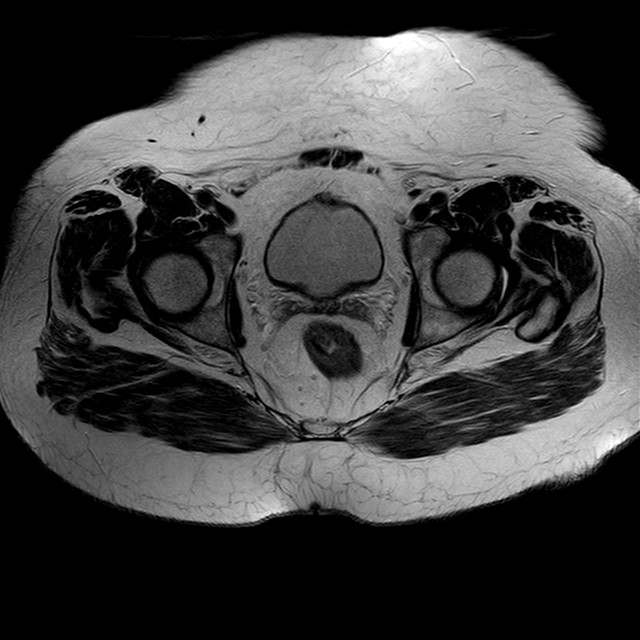

Esami: RMN BACINO

eT2w TSE

Evidenti e simmetriche alterazioni osteofitosiche in regione coxo femorale con riduzione delle rime articolari. Degenerazione completa del cercine glenoideo. Non attuali segni di versamento articolare. Non segni di edema osseo che escludono attuale algodistrofia od osteonecrosi. Lieve e simmetrica riduzione del trofismo della muscolatura glutea.